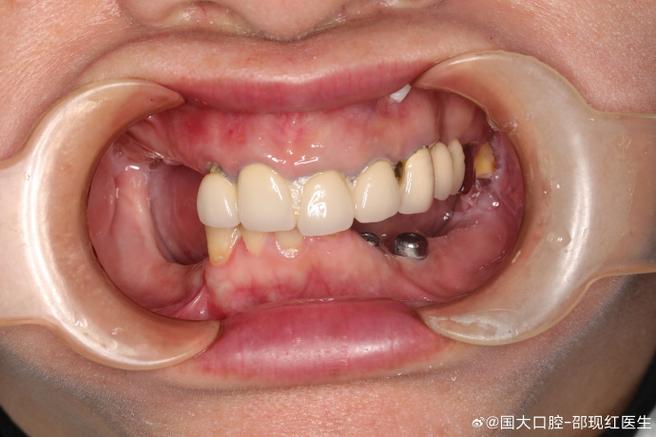

- 种植支持的固定桥: 如果骨条件好,通常选择在缺牙区植入2颗或更多种植体,上面做金属烤瓷或全瓷固定桥,这是最接近天然牙感觉的修复方式。

- 种植支持的覆盖义齿: 如果骨条件一般或患者希望费用相对较低,可以在缺牙区植入2颗(下颌)或4颗(上颌)种植体,然后在活动义齿的基托内安装磁性附着体、杆卡附着体或球帽附着体,使义齿获得强大的固位力,这比纯活动义齿舒适稳定得多。